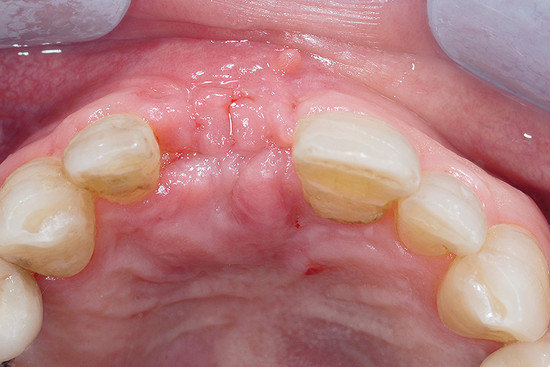

Widok w trakcie operacji na implant wstawiony w odbudowaną kość, która wymaga modelowania, aby poprawić efekt estetyczny w obrębie zęba 11.

Wypełnienie grzbietu małymi granulkami Geistlich Bio-Oss®, który pokryty jest Geistlich Bio-Gide® Compressed, aby poprawić kontur tkanki twardej oraz efekt estetyczny.

Stabilizacja Geistlich Bio-Gide® Compressed pinami (przedsionkowo) oraz wchłanialnymi nićmi (podniebiennie) w celu unieruchomienia wypełnienia.

Pierwotne zamknięcie rany jest uzyskane dzięki mobilizacji płata oraz wewnętrznym i zewnętrznym szwom.

Kontrola uzupełnionego miejsca po 8 dniach. Świetne gojenie się rany pierwotnej, bez rozejścia się brzegów.